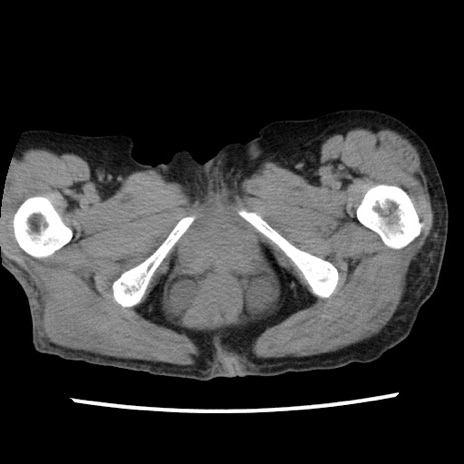

矢状断像

【症例】80歳代女性

【主訴】腹痛

【現病歴】8時間前から腹痛あり来院。

【既往歴】糖尿病、脂質異常症、子宮体癌にて子宮全摘術

【身体所見】意識清明・会話良好だが腹痛で苦悶様、全腹部にわたって反跳痛と圧痛あり

【データ】WBC 13600、CRP 0.14、LDH 224、CK 90